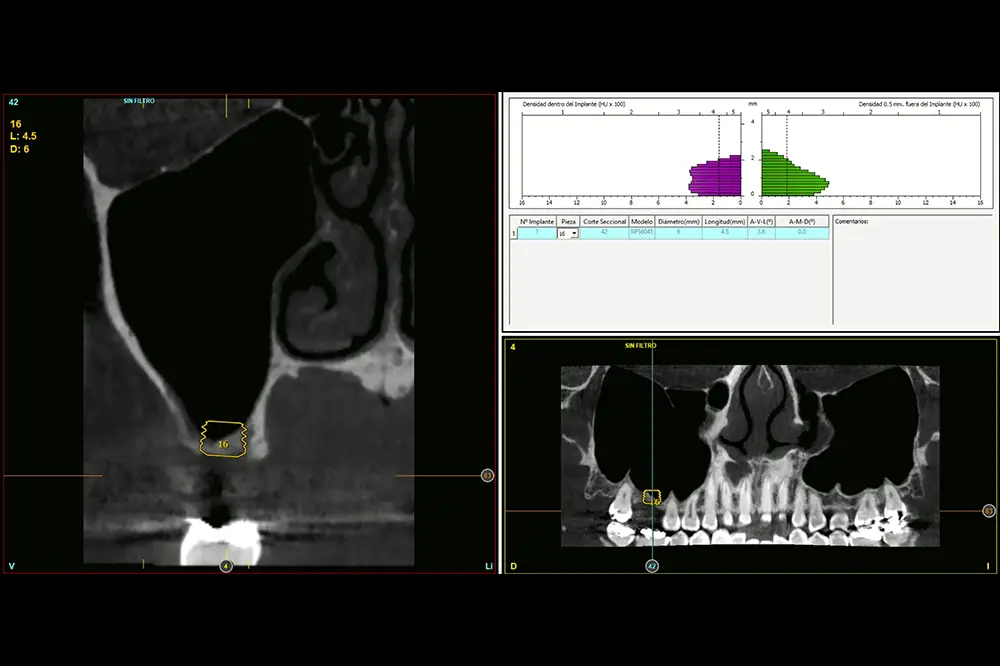

Procedemos a la extracción de la pieza dental y regeneración con PRGF-Endoret, además de un legrado minucioso de la lesión periapical para lograr una mejor regeneración del alveolo dental. Cuatro meses después de la extracción y regeneración del alveolo, se realiza un nuevo TAC de control para constatar la altura ósea residual y planificar la cirugía del implante. En la medición de la altura en la zona de inserción del implante podemos observar como existe únicamente 1,5 mm a nivel de la zona más vestibular de la cresta y de 3 mm en la zona palatina. Esto nos hace planificar un implante de 4,5 mm de altura (fig. 3) en esta posición, anclado sobre todo en la zona más palatina (anclaje vestíbulo-palatino), que nos permitirá realizar un abordaje crestal del seno con hueso autólogo como material de injerto, utilizando el implante como implante transicional que va a impedir el colapso del injerto primario (fig. 4).

Fig. 3. Medición en el TAC de planificación de la altura del tramo edéntulo para planificar el implante a insertar. Podemos ver cómo en la zona más vestibular únicamente disponemos de 1,5 mm y en la zona más palatina de 3 mm. Esto nos permitirá anclar el implante.

Fig. 4. Planificación del implante de 4,5 mm de longitud. Como vemos, la mayor parte de su anclaje viene dada por la bicorticalidad vestíbulo-lingual y además será utilizado como mantenedor del injerto primario (evitando el colapso) para posteriormente insertar uno de mayor longitud.

Se realizó la inserción implantaria mediante un abordaje transalveolar de elevación crestal descrito por nuestro grupo de estudio29,30. El procedimiento comenzó con el fresado del lecho receptor a bajas revoluciones, siguiendo un protocolo de fresado biológico orientado a preservar la vitalidad ósea. Se mantuvieron aproximadamente 1,5 mm de hueso residual en contacto con la membrana de Schneider para evitar su perforación durante las fases iniciales. El milímetro final fue abordado con una fresa de corte frontal diseñada específicamente para trabajar en proximidad a estructuras anatómicas sensibles, minimizando el riesgo de lesión de la membrana sinusal. A través del acceso crestal, se aplicó una presión controlada y progresiva (con la posibilidad de interponer una membrana de fibrina como elemento amortiguador) para inducir un despegamiento delicado de la membrana de Schneider. Este paso permitió completar el fresado de la cortical remanente con mayor seguridad y sin comprometer la integridad de la membrana. Una vez conseguida la elevación controlada, se procedió a la colocación del material de injerto. En este caso se utilizó hueso autólogo particulado y PRGF-Endoret. Tras la correcta adaptación del injerto, se insertó el implante alcanzando la estabilidad primaria planificada. Cinco meses tras la cirugía de elevación crestal con inserción del implante de 4,5 mm, podemos observar un TAC de control donde se aprecia el volumen óseo incrementado, llegando hasta 9,1 mm (fig. 5).

Fig. 5. Injerto óseo una vez consolidado tras la cirugía inicial. Ahora disponemos de 9 mm de volumen óseo y el implante puede ser recambiado por otro de mayor longitud para que la rehabilitación unitaria sea más favorable.